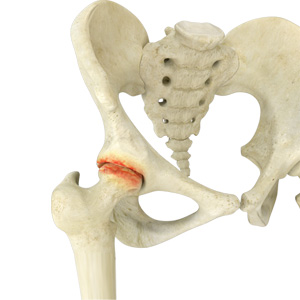

Hip Arthritis

Osteoarthritis, also called degenerative joint disease, is the most common form of arthritis. It occurs most often in the elderly. This disease affects the tissue covering the ends of bones in a joint called cartilage.

Avascular Necrosis

Avascular necrosis, also called osteonecrosis, is a condition in which bone death occurs because of inadequate blood supply to it. Lack of blood flow may occur when there is a fracture in the bone or a joint dislocation that may damage nearby blood vessels.